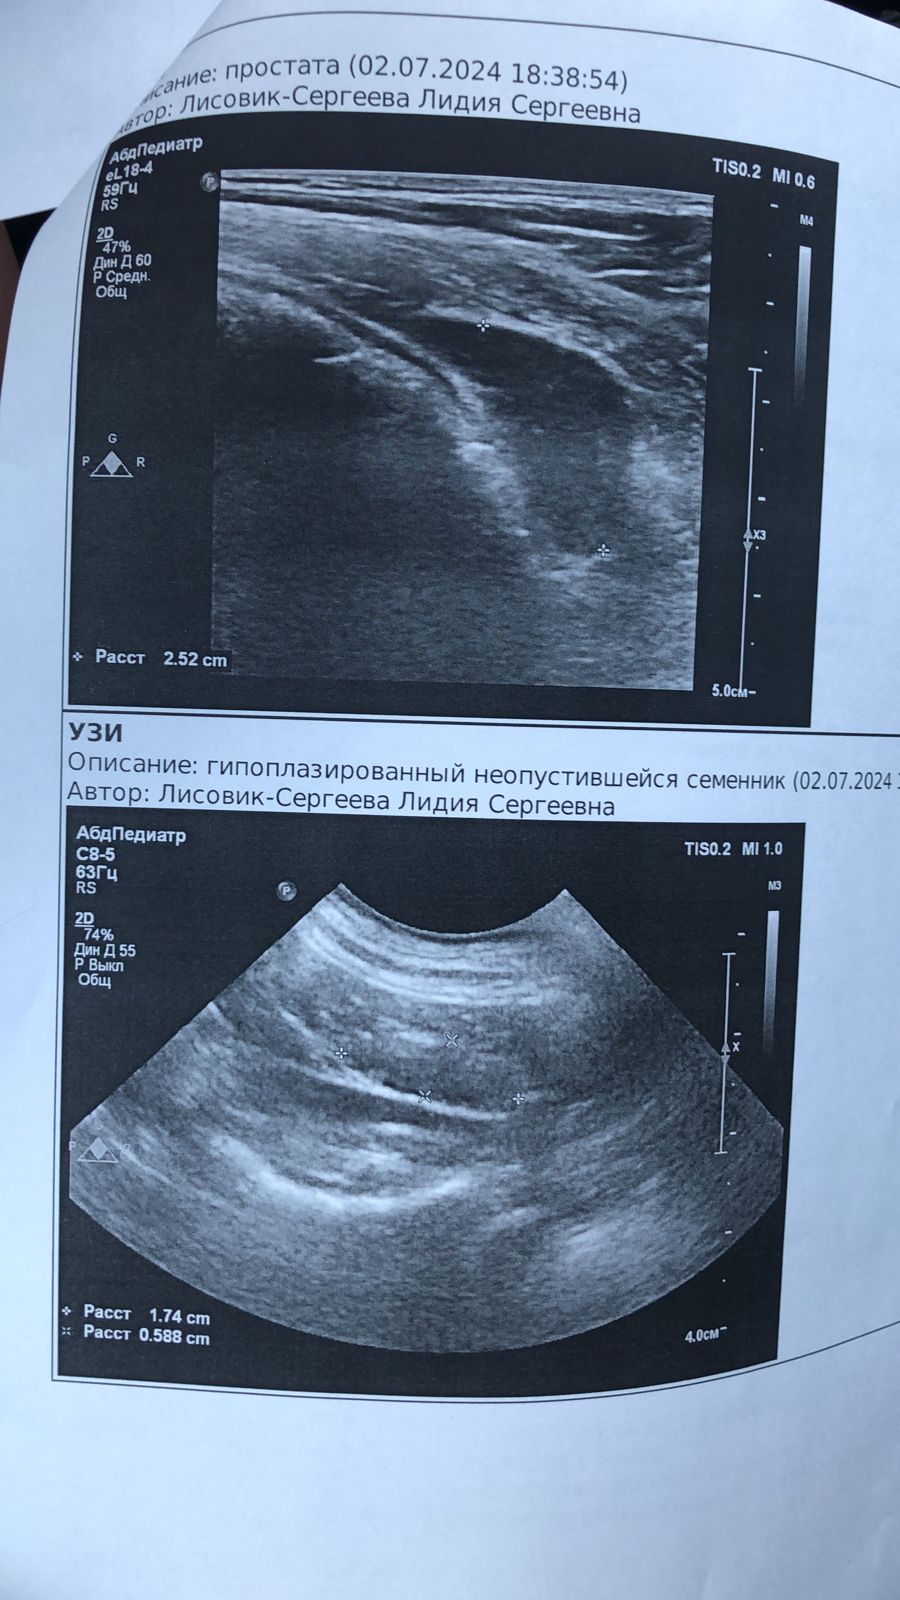

Поездка к онкологу и на УЗИ

Вложения

IMG-20240702-WA0025.jpg

IMG-20240702-WA0023.jpg

IMG-20240702-WA0024.jpg

IMG-20240702-WA0022.jpg

IMG-20240702-WA0021.jpg